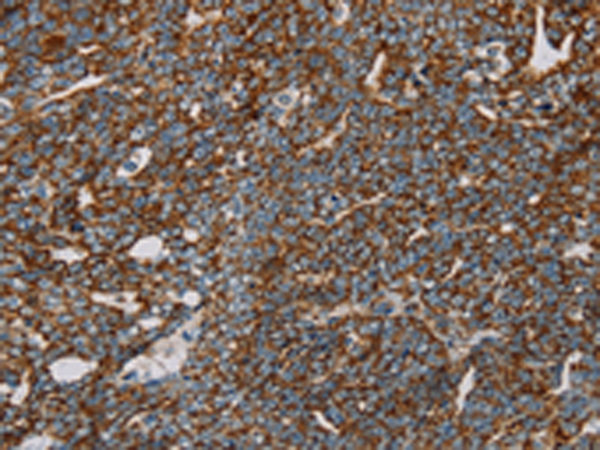

IHC positive control: |

Human cervical cancer and human thyroid cancer |

IHC Recommend dilution: |

50-200 |